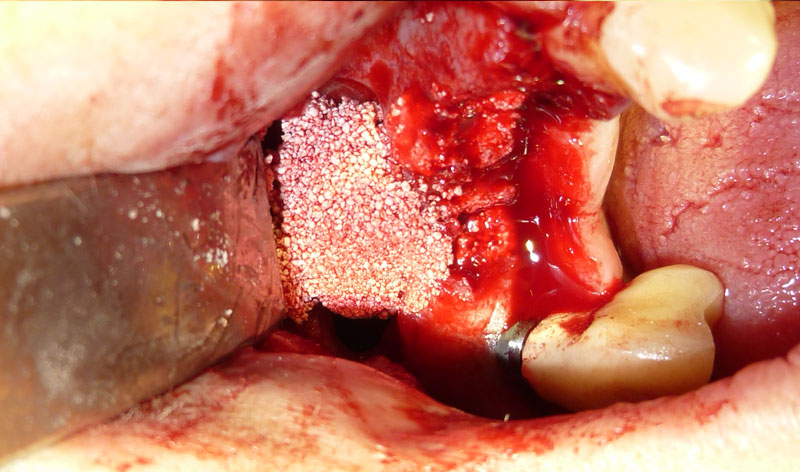

Procedimiento: se realiza una incisión en la encía, se aborda el hueso maxilar superior realizando una pequeña apertura en el margen externo del maxilar, y se introduce un cemento formado por el propio hueso y sangre del paciente, y un material óseo conductor, que proporciona una serie de condiciones básicas para la formación de hueso.

Una vez realizada la intervención, en algunos casos se pueden colocar los implantes a la misma vez y en otros, es necesario esperar seis meses para que el material óseo forme un hueso con buena calidad que asegure el éxito de los implantes.